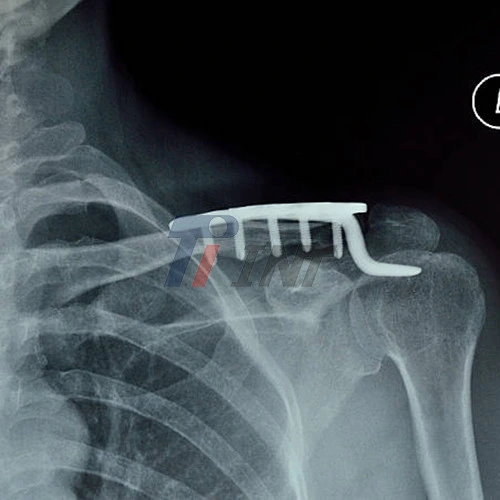

Clavicle Surgery Titanium Plate Fixation

Clavicle surgery titanium plate has become the gold standard for surgical fixation of clavicle fractures. These plates offer several advantages:

During surgery, the fractured clavicle is realigned and the titanium plate is securely attached using screws. This provides stable fixation to promote proper bone healing. The clavicle surgery titanium plate acts as an internal splint, allowing for early mobilization and rehabilitation.